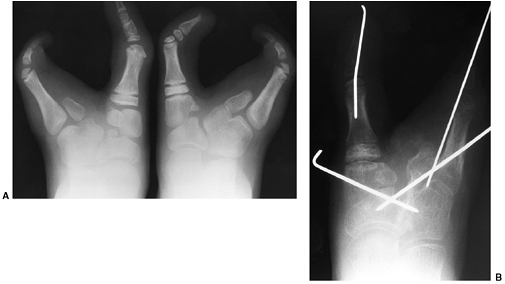

to casting for a period of time until healing has occurred and

exercises begun. Kirschner-wire (K-wire) stabilization of the foot with

one or two wires following surgery has been generally advocated.

Generally, wire stabilization of the talonavicular joint is done to

prevent talonavicular subluxation. The residual deformity or increasing

postoperative deformity from subluxation of the navicular is severe and

has prompted most surgeons to stabilize the talonavicular joint

following release. A second wire may be placed through the subtalar

joint to prevent lateral translation of the calcaneus, particularly if

the interosseous ligament is divided. Finally a wire may be placed

across the calcaneocuboid joint in cases where marked deformity of the

lateral column is documented and surgical correction required.